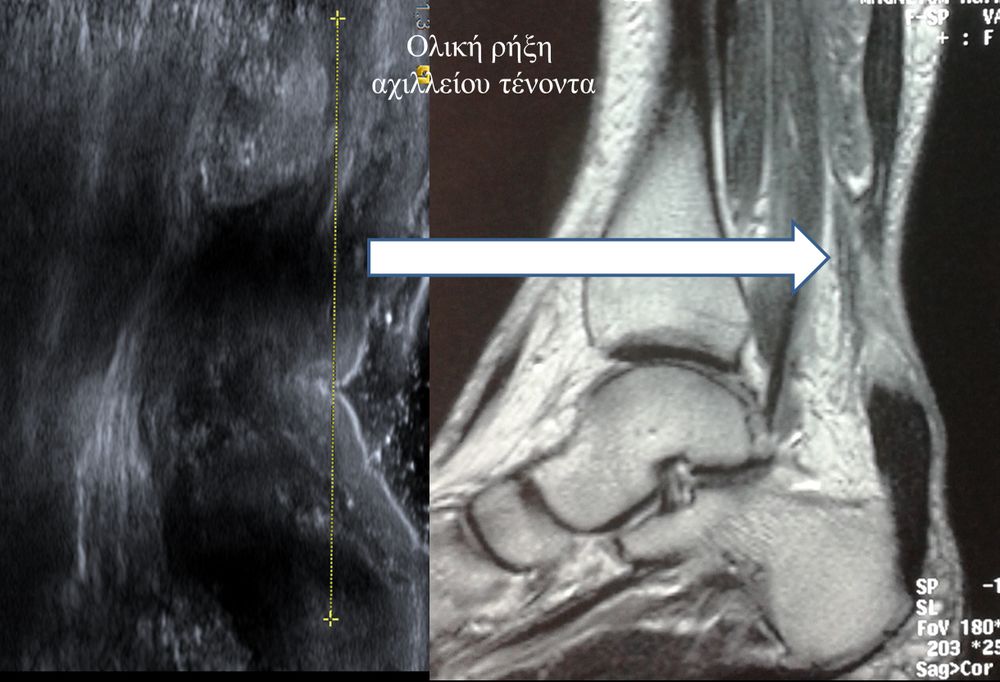

Είναι μια νέα μέθοδος που χρησιμοποιεί υψηλής ευκρίνειας υπερήχους για τη διάγνωση μυοσκελετικών παθήσεων που αφορούν τένοντες, μυς, συνδέσμους, νεύρα και περιφερικές αρθρώσεις. Η μέθοδος αναπτύχθηκε τα τελευταία χρόνια και αποτελεί αναπόσπαστο μέρος στη διαφορική διάγνωση παθήσεων που αφορούν τηνορθοπαιδική, αθλητιατρική, ρευματολογία και παιδιατρική.

Πρόκειται για υπερηχογράφημα υψηλής ευκρίνειας που επιτρέπει την λεπτομερέστατη απεικόνιση (σε επίπεδο χιλιοστού) ακόμη και πολύ μικρών/επιφανειακών ανατομικών δομών και απαιτεί ειδικό υπερηχογραφικό εξοπλισμό καθώς και εξειδίκευση του ακτινολόγου. Η εξέταση γίνεται με δυναμικό τρόπο, δηλ εκτελούνται δοκιμασίες κίνησης του μέλους που πάσχει, ώστε να αποκαλυφθεί η παθολογίαακόμη και όταν δεν είναι εμφανής σε θέση ηρεμίας. Επιπλέον, η εξέταση είναι ανώδυνη και ασφαλής και δεν περιλαμβάνει ακτινοβολία (CT), μαγνητικό πεδίο (MRI) ή παραμονή σε κλειστό χώρο και είναι πολύ ανεκτή τόσο σε ενήλικες όσο και σε παιδιά.

- Ακρου Ποδός/ Πέλματος (πχ απονευρωσίτιδα)